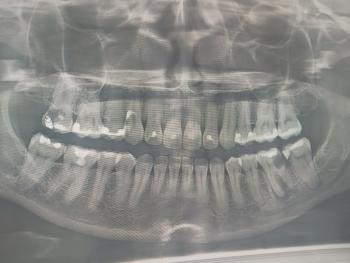

Extraction of Ectopic Nasal/Erupting 21 in a 7-Year-Old — Post-op Care and 14-Day Risk Management

A 7-year-old male with an ectopically erupting/extruded permanent tooth (FDI 21) that presented in or near the nasal cavity/vestibule and was extracted.

Photo shows the nostril/oral vestibule area with the extraction site and adjacent mucosa — looks like soft-tissue involvement of the nose/nasal floor region rather than a simple intraoral socket alone.

Because this involves the nasal mucosa / floor of nose, management and follow-up should consider both dental and ENT issues.

Periapical/panoramic radiograph or CBCT if retained fragments / concern for adjacent developing tooth bud.